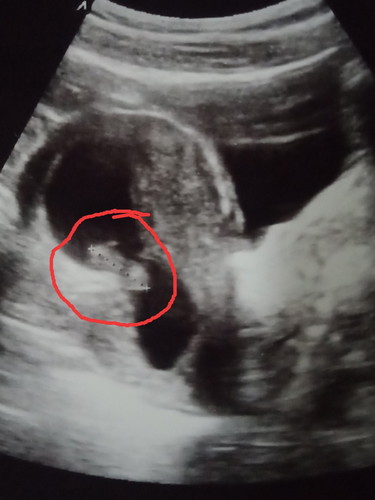

ตั้งครรภ์น้องได้ 3 เดือนกว่า

สวัสดีค่ะคุณแม่ทุกคนค่ะ ตั้งครรภ์น้องได้ 3 เดือนกว่าตอนนี้น้องหลุดแล้วค่ะ??